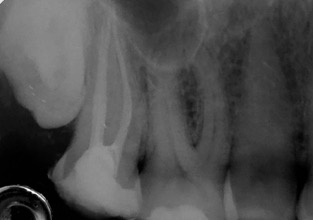

Una corretta terapia canalare con un perfetto sigillo a livello degli apici delle radici è fondamentale. I denti devitalizzati impropriamente possono creare ulteriori problemi che poi andranno a ripercuotersi sulle cure effettuate successivamente come le ricostruzioni e le corone protesiche con conseguente fallimento del piano terapeutico.

Capita spesso di incontrare denti già devitalizzati in maniera impropria che necessitano, seppur asintomatici, di essere ritrattati per evitare che i granulomi infetti visibili radiograficamente si evolvano riassorbendo tutto l’osso sottostante.

Un adeguata endondonzia serve per salvare quei denti che altrimenti sarebbero destinati ad essere estratti. Quando un dente viene devitalizzato viene privato della sua irrorazione sanguigna e del nutrimento, rendendo la sua struttura più “vetrosa” quindi più fragile e soggetta a fratture. Per questo motivo è consigliabile nella maggior parte dei casi capsulare i denti una volta che hanno perso la loro vitalità.